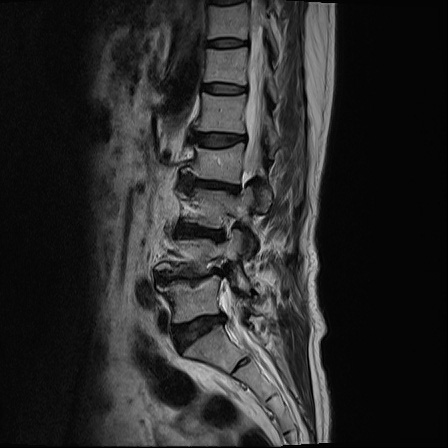

Ӵϲ ɿ ô ô 㸮 ٸ ̾ϴ. ϵ Ͻð ܻ 㸮 20⵿ ͽϴ. mri ˻ ɿ Ȳ ʹ ؼ Ȳ̶ ߽ϴ. ϻȰ ϰ 鼭 ½ϴ. ̴ ø鼭 Ͻô Ȳ ̷ ġ ص ȸ ϴ. δ Ҵµ, ù ȸԲ ˷ֽ ϰ β ϰ, ˷ֽ ü ƮĪ ϸ鼭 ȭǸ鼭 Ӵϲ ȸų ְ ǰ, β 鼭 ʴ β ؾϴ ŷο 1ϸ ijħ ڸ ǥ Ʈ ߽ϴ. ȸ ȭϽø鼭 Ϸ簡 ٸ ȸǽð 4ְ Ǿ Ǯ鼭 ¦ ҽϴ. ħ ȸ ȭϸ鼭 ڼ ü ƮĪ ϴ. ȥڼ Ͻʴϴ. ٳø鼭 ó Ͻ ʴϴ. ̾ ְ ̳ ߵ ʰ ϴ ȸԲ Ͻʴϴ. ʹ ϸ鼭 ϴ. Ȩ - ϱ ٴ Ȳ MRIԴϴ. |